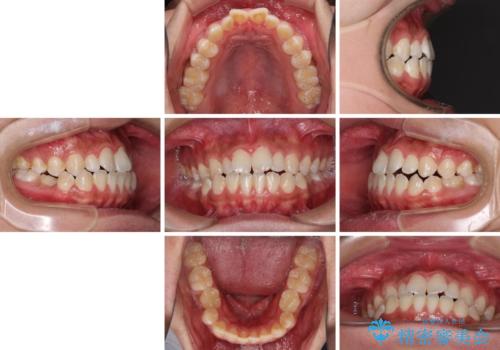

口元の突出感を改善 受け口傾向の咬み合わせの抜歯矯正

- 受け口傾向の咬み合わせと口元の突出感を気にして来院された患者様です。

受け口傾向特有の狭い上顎歯列であったため、歯列の拡大を補助装置で行い、下顎歯列全体を後方に移動させることとしました。

奥歯の咬み合わせを改善させた後、上下左右の小臼歯(下顎は残存乳歯)を計4本抜歯し、ワイヤー装置にて口元の突出感を改善しながら咬み合わせを整えることとしました。